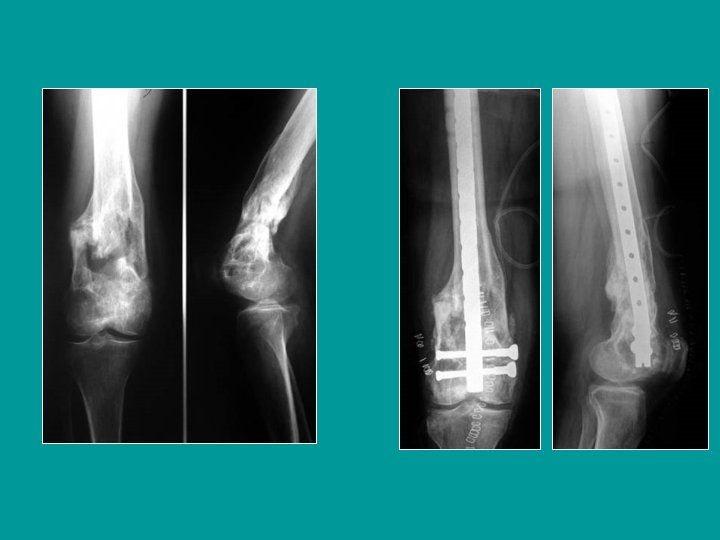

12 ans : trauma en hyperextension du genou Salter I très déplacé

Réduction des déplacements en hyperextension Traction dans l’axe de la jambe le genou étant fléchi Pendant que l’on replace l’épiphyse en poussant en bas et en arrière +/- correction latérale

Embrochage percutané

Résultat après 5 semaines et l’ablation des broches

Salter I très déplacé : réduction et embrochage percutané